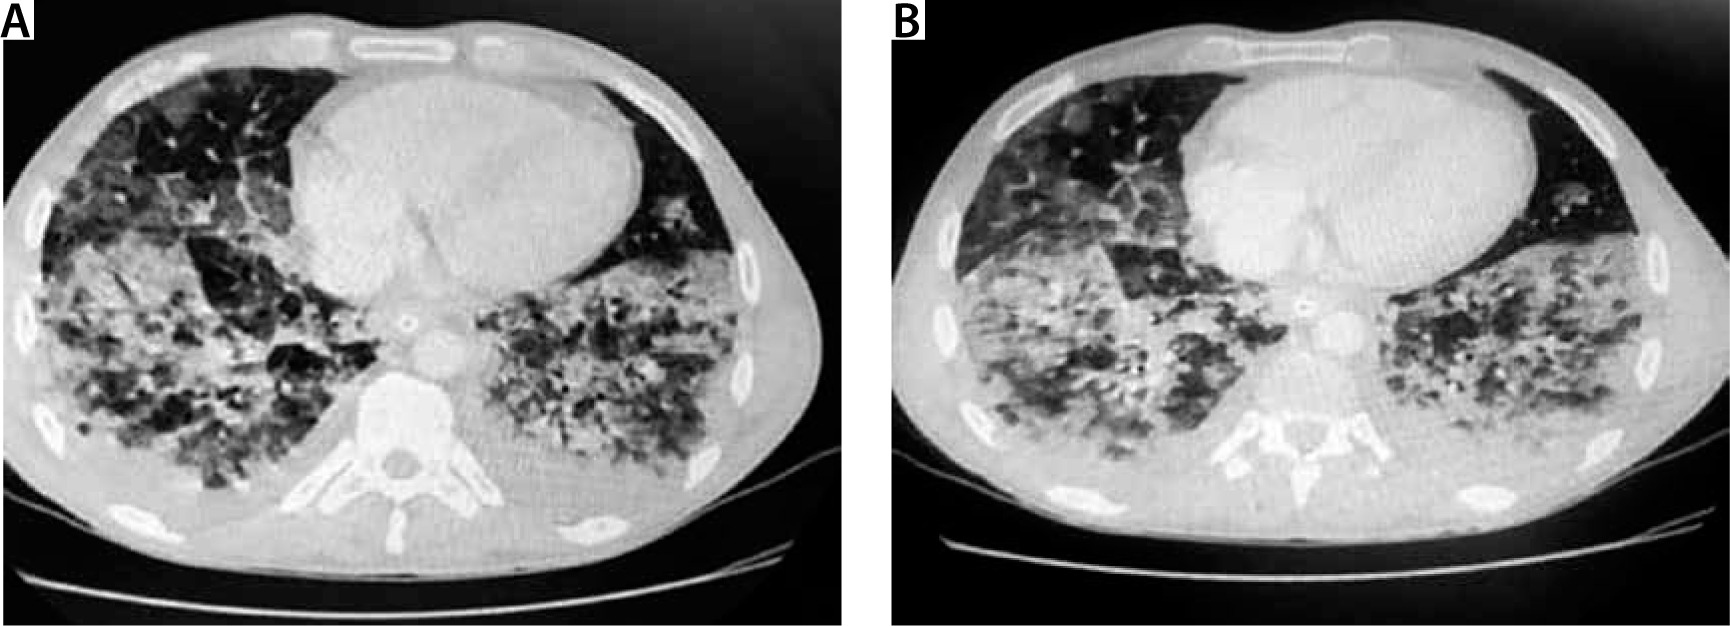

FIGURE 3

Chest computed tomography. A 32-year-old patient without concomitant diseases. History of e-cigarette use

It is not easy to diagnose e-cigarette-associated lung injury, as the initial symptoms are not pathognomonic. Most clinical descriptions stress the development and increasing severity of general symptoms, e.g. dyspnoea, non-productive (dry) cough and chest pain. In addition, gastrointestinal disorders, nausea, vomiting, generalised abdominal pain, and subjective heat sensations are observed. However, symptoms of the upper airway infection are rare; therefore, the diagnosis, often crucial for further treatment strategy, is delayed [11, 12, 17]. Due to vague symptoms, the outpatient broad-spectrum antibiotic therapy is prescribed. The lack of improvement following antibiotic therapy and intensified symptoms of respiratory failure are characteristic of e-cigarette-induced respiratory pathologies. Laboratory analyses demonstrate moderate leucocytosis with a high percentage of neutrophils, increased C-reactive protein (CRP) values at relatively low levels of procalcitonin. Radiologic lung changes are observed in over 90% of all the patients treated and are extremely important [32]. The most common X-ray finding is diverse bilateral shadowing, which is the basis for performing lung computed tomography (CT). Although not characteristic, the CT scan is important for diagnostic considerations. The changes observed are diffuse consolidations, ground glass or crazy paving patterns [8, 9, 12, 33]. In such cases, sputum evaluation and bronchoscopy with BAL should be performed and cellular elements searched for, e.g. lipid-laden macrophages, although eosinophils, neutrophils or lymphocytes predominate in some cases [17, 24, 31]. The presence of lipophages is a noteworthy and quite repeating feature found in the literature cases, though their pathophysiological significance has not been fully elucidated. Some centres have considered their presence a characteristic feature useful for the diagnosis of vaping-associated lung injury; however, recent reports disprove such explicit opinions [9, 12, 35, 36]. The identification of lipophages in sputum, BAL or biopsy specimens, combined with other elements of biochemical and radiological assessment, may become a useful marker of this disease. Furthermore, lipoid pneumonia, often initially diagnosed as interstitial inflammation, can also be confused with ARDS, lung cancer or pulmonary granuloma; therefore, differential diagnosis ought to be extremely meticulous. Lipoid pneumonia can also be exogenous, as in the most bizarre case of fatty fluid absorption by a fire swallower [37]. BAL combined with an open lung biopsy is likely to visualise lung-damaging changes; due to their primary cause, they are acronymically called EVALI or less commonly vaping-related acute lung injury (VpALI) [7, 8, 11, 12]. The consequences of EVALI vary and often depend on individually differentiated reactions to vaping. They may be associated with the development of acute eosinophilic pneumonia, fibrous pneumonia, lipoid (lipid) pneumonia, diffuse alveolar damage (including diffuse alveolar haemorrhage), ARDS, hypersensitivity pneumonitis, also known extrinsic allergic alveolitis, and giant cell interstitial pneumonia [6, 8, 11–13, 17]. Noteworthy, each of these diseases unrelated to vaping is extremely difficult to diagnose. However, it should be remembered that the history of e-cigarettes use can help to determine the cause of a given disease, although the coincidence is not absolute. At present, on the threshold of 2020, however, several elements seem to be likely to facilitate the diagnosis, despite diverse clinical manifestations and non-specific radiological and histopathological images. The majority of patients (> 80%) manifesting lung injury symptoms reported using nicotine, THC or CBD [8, 9, 22]. In the study groups, the concomitance of bacterial and viral infections was excluded, and the symptoms and imaging findings were suggestive of toxic lung injury. As highlighted above, due to mixing of many ingredients with compounds originally intended for inhalation and potential impurities, new compounds are formed. A thorough ex-post analysis has demonstrated that in addition to the above mentioned and expected chemicals, e-liquids contain variably occurring potentially toxic and interacting substances, occurring in variable amounts, such as carbonyls, volatile organic compounds (e.g. benzene and toluene), nanoparticles, trace elements, bacterial endotoxins, and fungal glucans. Moreover, the study findings have revealed that some flavouring substances, e.g. diacetyl, and 2,3 pentanediol, impair the pathway of expression of genes associated with the ciliary cells and cytoskeleton of alveolar epithelial cells, in addition to other components. irrespective of other components [38, 39]. It is also difficult to determine how important the type of e-cigarettes, frequency of exposure (dosage), origin and final composition of inhaled substances are. The available data predominantly pertain to young populations with no history of health issues yet still developing the EVALI symptoms. In each case, patients presented comparable clinical features and disease progression, which implies a similar pathophysiological mechanism of lung injury.